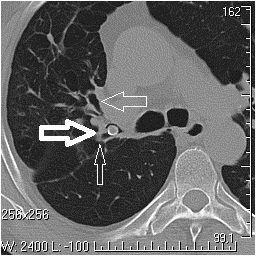

Исследование выявило в месте разветвления верхнедолевого бронха на S1–2 и S3 скорлупообразное тенеобразование повышенной плотности. Рентгенолог предположил инородное тело, рекомендовал бронхологическое обследование.

Толстая стрелка — инородное тело в просвете верхнедолевого бронха, средняя — бронх к S3 правого легкого, тонкая — устье бронха к S1–2 правого бронха.

Во время бронхоскопии из просвета верхнедолевого бронха правого легкого извлекли вишневую косточку — к величайшему удивлению пациента, который и не помнил, как ее вдохнул. Диагноз «туберкулез» снят.

Можно предположить, что аспирированная косточка привела к обтурации бронха и вызвала воспаление в типичном для инородных тел месте — нижней доле (правый главный бронх является как бы продолжением трахеи, отходит от нее под углом 30 градусов), — прокомментировал Андрей Лантухов. — Поэтому воспаление было длительным и не поддавалось терапии. Когда проходимость бронха восстанавливалась, все исчезало; рецидивы были обусловлены последующими эпизодами обтурации. Миграция косточки в верхнедолевой бронх при кашлевых толчках привела к распространению процесса в верхние отделы.